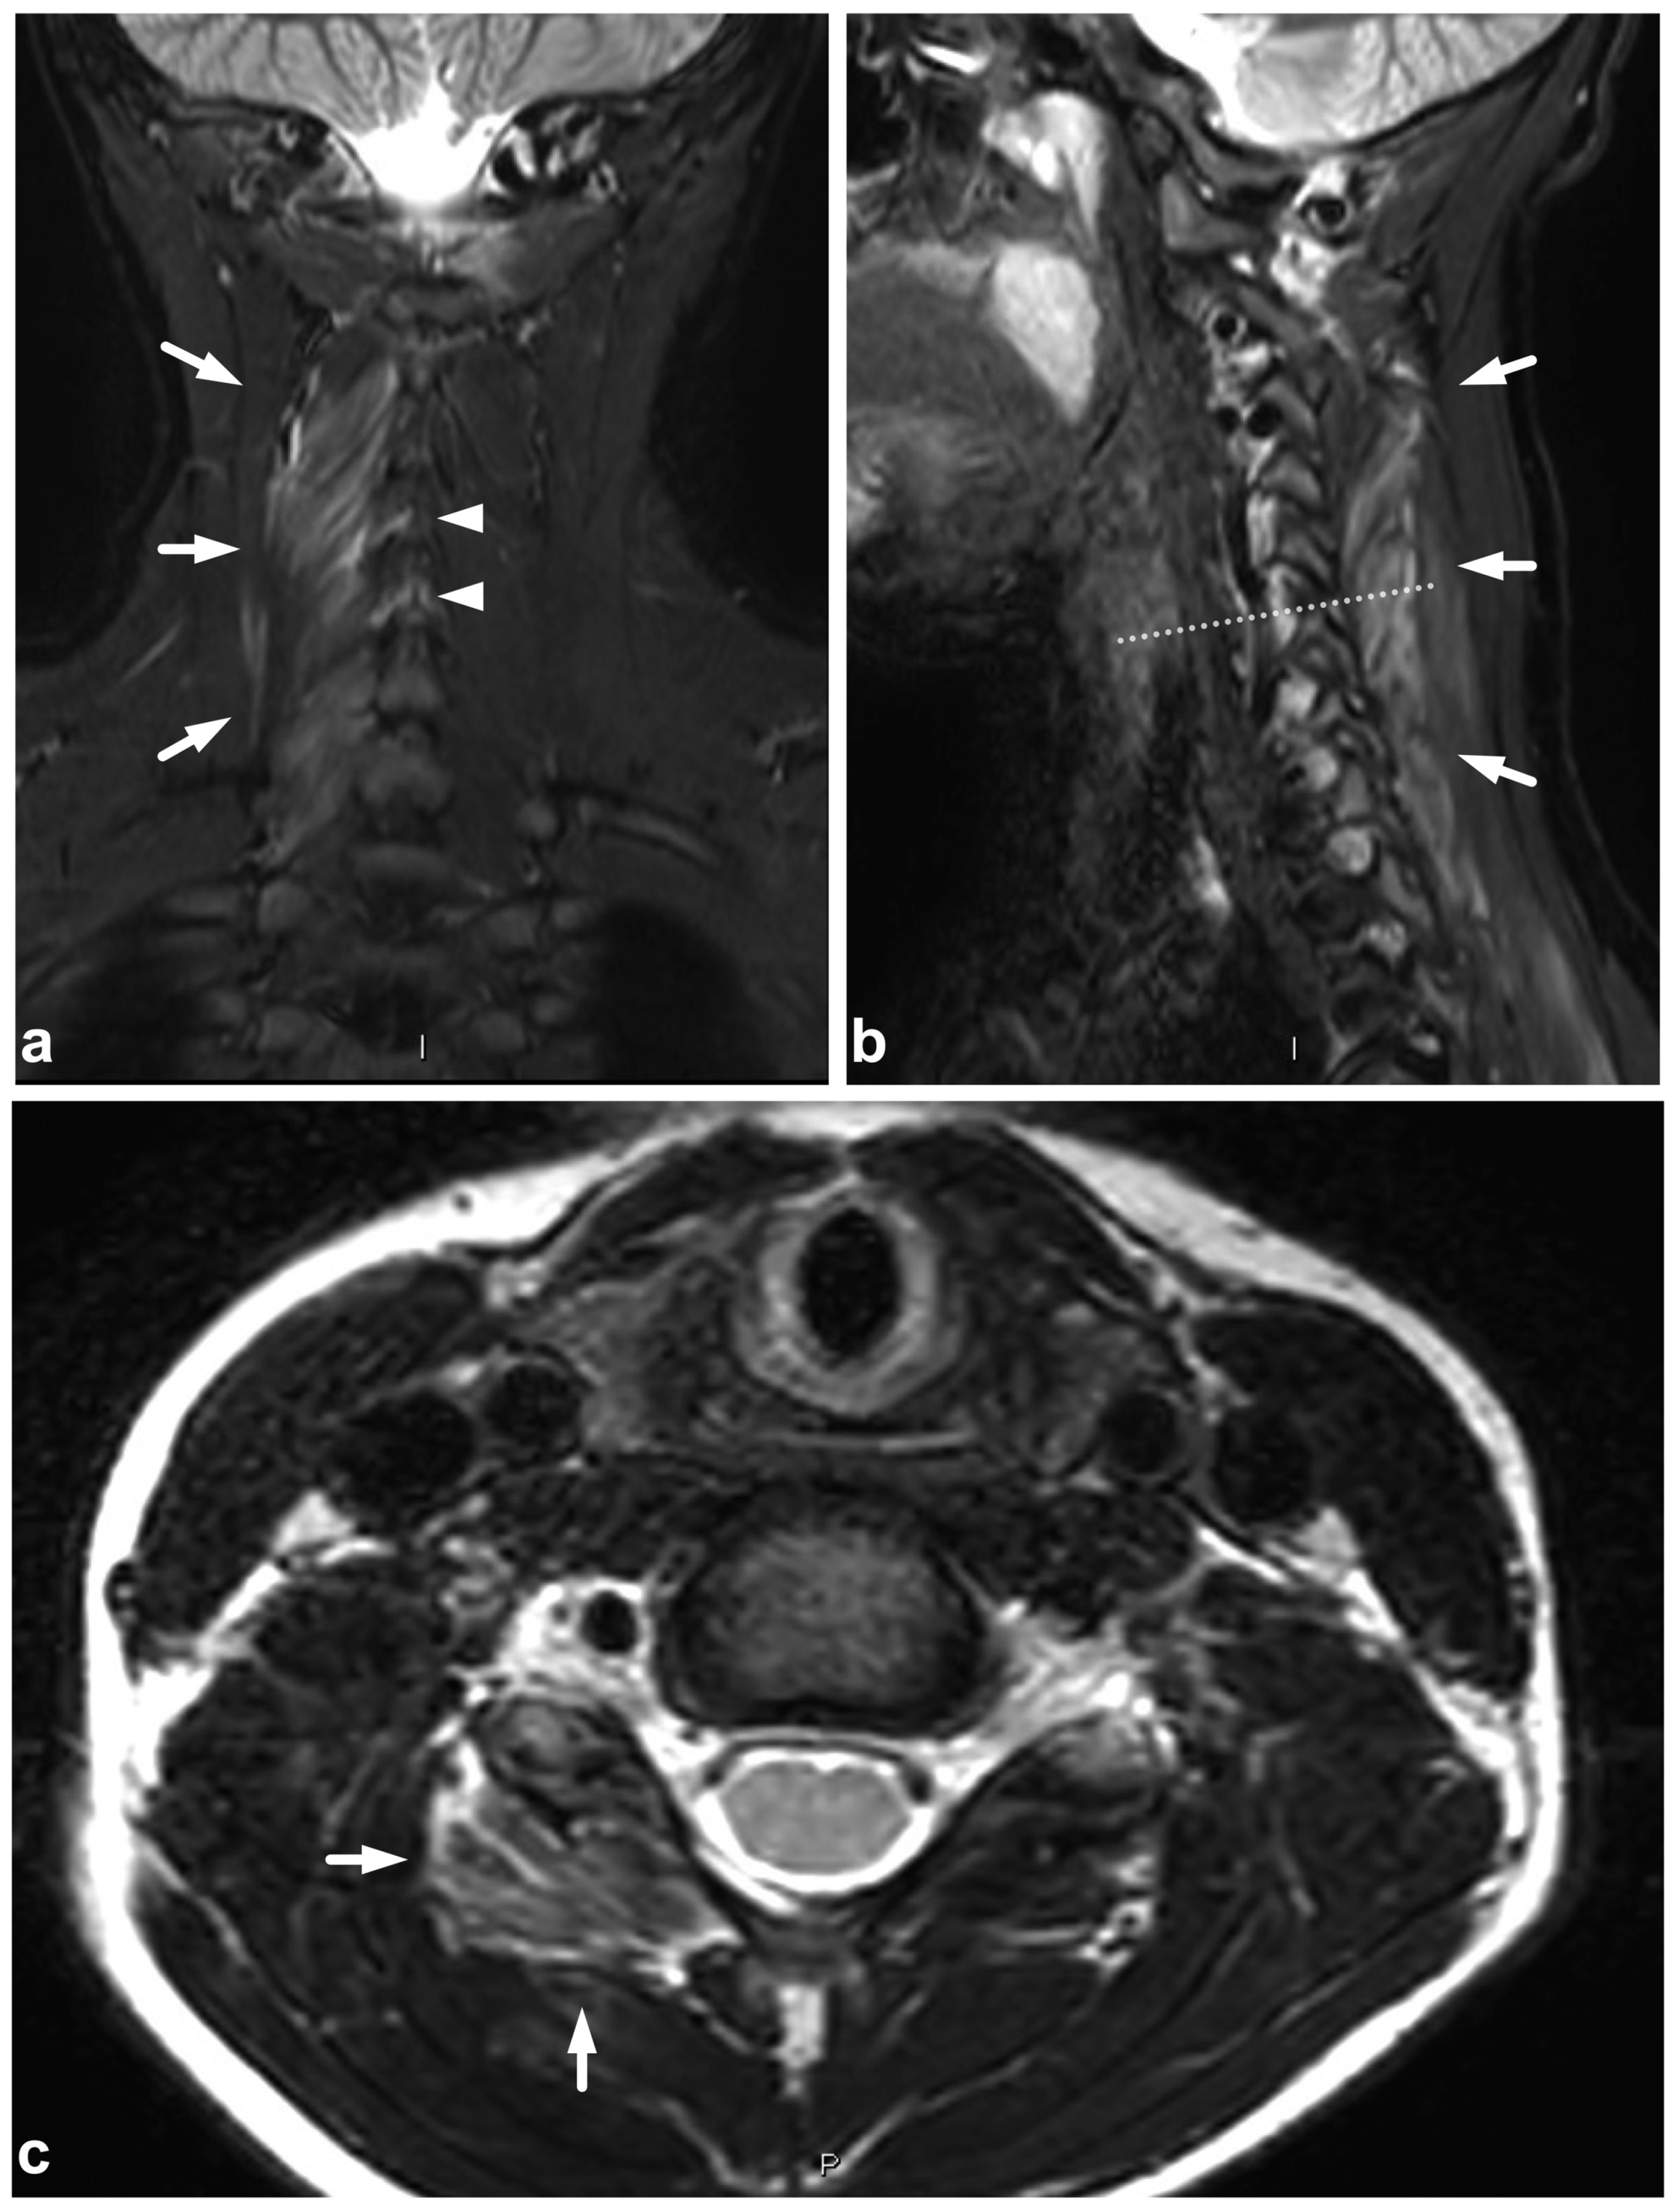

5.3. Nerve Plexus Injuries

5.4. Vascular Injuries